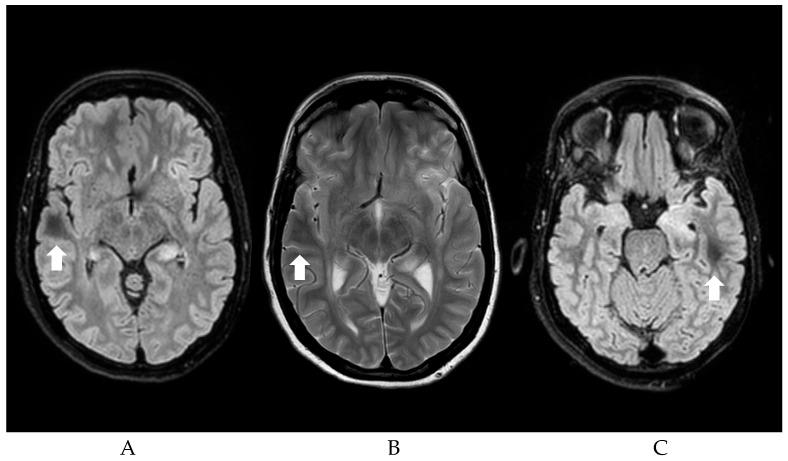

The radiological finding of Dark White Matter (DWM)-characteristic diffuse subcortical white matter hypointensity on T2/FLAIR sequences-is underrecognized, but has important clinical implications. Recent systematic evidence shows that over 60% of previously published cases showed seizures in association with DWM findings-it is also particularly predictive of the underlying etiology, particularly non-ketotic hyperglycemic hyperosmolar state (NKH). Based on our previous work, we reinterpret the data, focusing only on patients with seizures and DWM, to summarize the most essential and distinguishing features of these patients. Both cortical and subcortical abnormalities in DWM are more frequently associated with anti-MOG encephalitis. DWM with or without cortical involvement is more commonly found in NKH among patients with seizures. This updated systematic review will describe the proposed pathophysiological mechanisms, clinical associations, and implications for DWM in patients with seizures, and highlight how early recognition of DWM may allow for targeted diagnostic strategies and treatment options. We expanded our previous search with details regarding seizure features, our results show that DWM is associated with repetitive seizures and Status Epilepticus (both convulsive and non), in line with other peri-ictal MRI abnormalities associated with prolonged seizure activity. DWM-associated seizures are mostly focal, rather than generalized. Moreover, the high percentage of clinical recovery at follow-up suggests that DWM may be predictive of a good outcome, especially in NKH cases, although this needs to be confirmed in future studies.

暗白质(DWM)在T2/液体衰减反转恢复(FLAIR)序列上的特征性弥漫性皮质下白质低信号这一影像学表现尚未得到充分认识,但具有重要的临床意义。最近的系统证据表明,超过60%的既往发表病例显示癫痫发作与DWM表现相关——它对潜在病因也具有特别的预测性,尤其是非酮症高血糖高渗状态(NKH)。基于我们之前的工作,我们重新解读数据,仅关注癫痫发作和DWM患者,以总结这些患者最基本和独特的特征。DWM中的皮质和皮质下异常更常与抗髓鞘少突胶质细胞糖蛋白(MOG)脑炎相关。在癫痫发作患者中,伴或不伴有皮质受累的DWM在NKH中更为常见。这篇更新的系统综述将描述DWM在癫痫发作患者中可能的病理生理机制、临床关联及意义,并强调早期识别DWM如何有助于制定有针对性的诊断策略和治疗方案。我们扩大了之前关于癫痫发作特征细节的搜索范围,结果显示DWM与重复性癫痫发作和癫痫持续状态(惊厥性和非惊厥性)相关,这与其他与长时间癫痫发作活动相关的发作期MRI异常一致。DWM相关的癫痫发作大多为局灶性,而非全身性。此外,随访时较高的临床恢复率表明DWM可能预示着良好的预后,尤其是在NKH病例中,尽管这需要在未来的研究中得到证实。